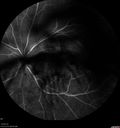

74 year old man with diabetes for about 40 years. No previous problems or treatments: EXTENDED HPI: Starting a little less then a week ago he woke up with something in the left eye. He saw a big blob in his vision. Since it started it is not getting better (also not getting any worse). The right eye is OK. This has not happened before. He is on ASA and Clopidogrel. VA OD: sc20/20+2 NscJ7-1 VA OS: sc20/63-2 NscJ2

Vitreous Hemorrhage with no evidence of PDR in the left eye374 views74 year old man with vision loss OS for about a week. The FA shows no PDR in the left eye but the right eye has very mild NVD. Diabetes for 40 years now on insulin.00000